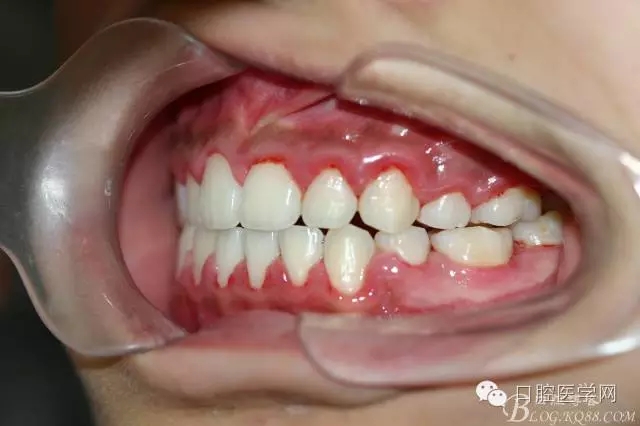

正畸查:替牙合。第一恒磨牙中性合。上牙弓尖圓型下牙弓方圓型。前牙覆合3度覆蓋7.5mm。下前牙咬到上舌側(cè)牙齦。上頜擁擠4.0mm,下頜擁擠

3.0mm。上頜稍前突下頜后縮,上下唇前突,上前牙覆蓋下唇,下唇外翻。面下三分之一過短,頦唇溝明顯,開唇露齒,頦饜窩明顯。顳下頜關(guān)節(jié)開閉口無彈響,無壓痛,開口型開口度正常。

正畸前照片: